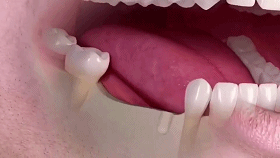

牙齿缺失会引起邻牙松动、对牙伸长、引发牙周病,最终牙齿脱落等一系列问题,还会因咬合紊乱致使面容苍老、咀嚼功能变差引发肠胃疾病,甚至影响身体健康。

种植牙是医学界公认的理想修复方式,被誉为“人类的第三副牙”。相比活动假牙不舒服、难清洗、容易引起口腔黏膜病变,种植牙更稳固耐用,舒适美观,咀嚼功能好,一次种植,终生受用。种植牙不仅是中老年人的专利,年轻人因意外、牙病等造成牙齿缺失,也能够通过种植牙进行修复治疗,重获美丽笑容。

(单颗种植示例)